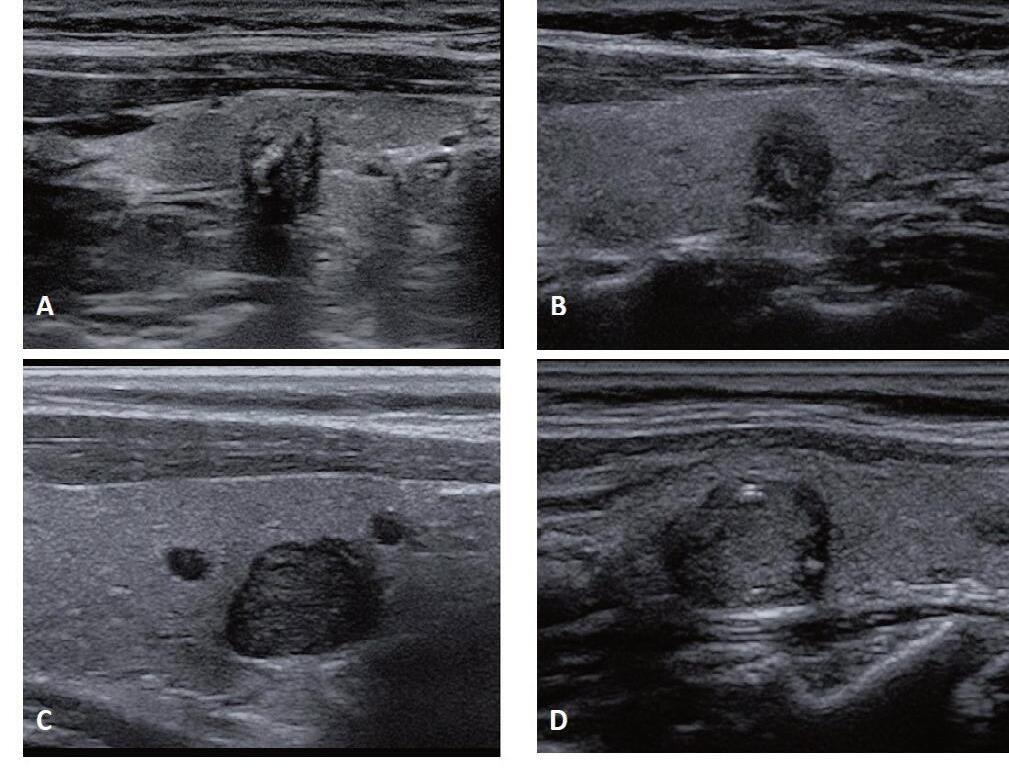

ECOGRAFIA DEL COLLO: STRUMENTO CHIAVE PER LA DIAGNOSI E IL MONITORAGGIO DEL CARCINOMA PAPILLARE DELLA TIROIDE

Giorgio Grani, Antonio Brunetti, Piernicola Garofalo, Giovanni Savoia, Michela Massa, Umberto Crocetti